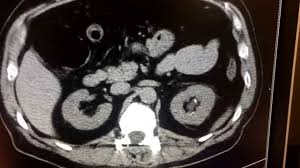

Mri Images Of Kidney Stones - Kidney stones usually originate in your kidneys.